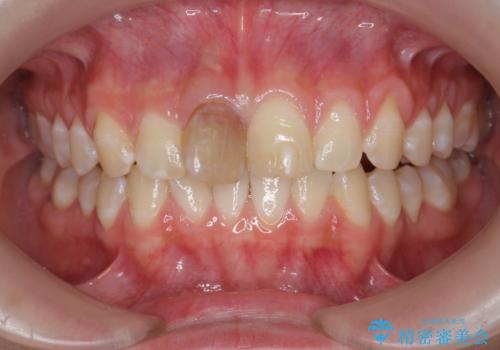

前歯をきれいにしたい ジルコニアクラウンによる審美治療

- 前歯の見た目の改善を求めて来院されました。

ジルコニアクラウンによる審美性の改善を計画します。

失活歯のため捻転を改善し、根管治療は特に希望されなかったのでそのままとしました。

今回失活歯であったため捻転を取り反対側の前歯に揃えて補綴を行うことができました。